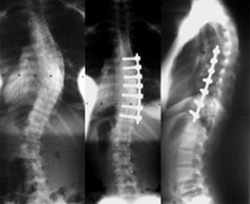

If you decide to have the procedure performed in the UK then the scoliosis surgery cost can be as much as £50,000. This is a lot of money to most of us and we may struggle to raise that amount of cash. It is also important to consider if this high scoliosis surgery cost is going to be actually worth it. There is no right answer to this because each individual is unique and the benefits they get from the surgery will vary. For some people scoliosis surgery can make a huge difference to their lives; not only their physical abilities but also their sense of mental well-being. For other people having the surgery the results can be disappointing or there have been complications that have arisen as a result of the surgery. With all operations there is always the chance that things will go wrong – and this scoliosis surgery is no different. The surgical team will be able to provide their opinion of the risks and potential benefits in each case – it will be then up to the individual to decide if it is worth it.

Some people may decide to go abroad in order to get the procedure done for a reduced scoliosis surgery cost. This is not a decision that should be taken lightly because there are further risks associated with having this procedure done abroad; especially in those parts of the world that have a lower cost of living. The most important risk is that the surgical team might not be competent enough, or have the right equipment, if they are able to provide the procedure cheaply. There is also the risk of developing complications post-procedure and being stuck in a foreign country away from loved ones.

The scoliosis surgery cost in the US is about the same as the UK, but there are other countries that offer the procedure for considerably less. If you are going to consider one of these other options you are advised to do your research to ensure that the operation will be performed by competent surgeons in a good hospital. Sometimes the reason why hospitals can offer procedures at a cheap price is because they offer low wages to employees and avoid buying needed equipment and supplies; on the other hand, there are some hospitals abroad that can offer a first-class service at a cheaper price than the UK.